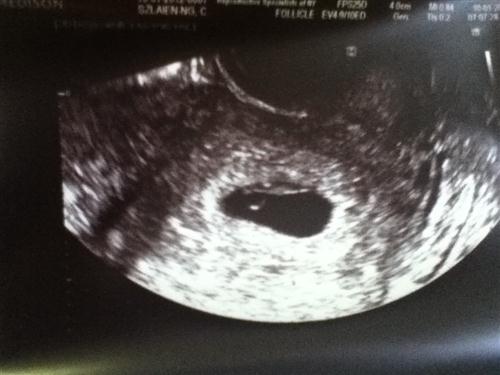

Sono #1